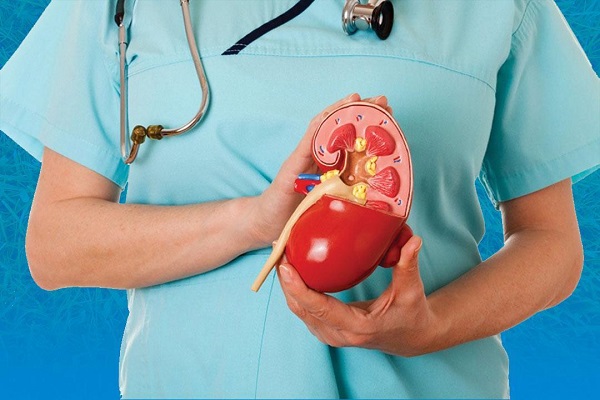

- مستشفى القنطرة غرب تحصل على معايير الاعتماد والرقابة الصحية..صور